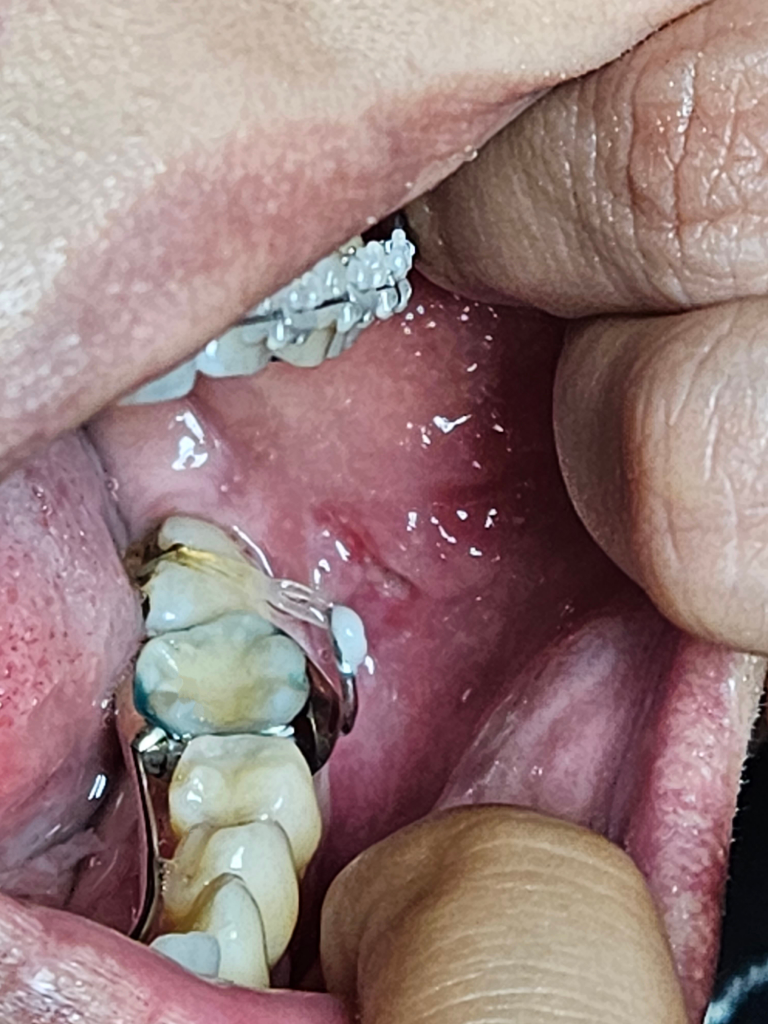

교정보철로 인한 볼안쪽 찢어졌는데 상처 어떡하죠?

어금니 쓰러짐으로 인해 이제 1주일째 교정중인데 왼쪽 볼 안쪽이 보철에 의해 살이 찢어졌어요.. 어제 알보칠로 지졌는데도 아직도 아프고 살이 붓고 찢어져 있어요.. 다시 병원가서 치료를 받아야 할지 아님 그냥 버텨야할지 모르겠는데 어떡하나요..

• 1번 째 사진